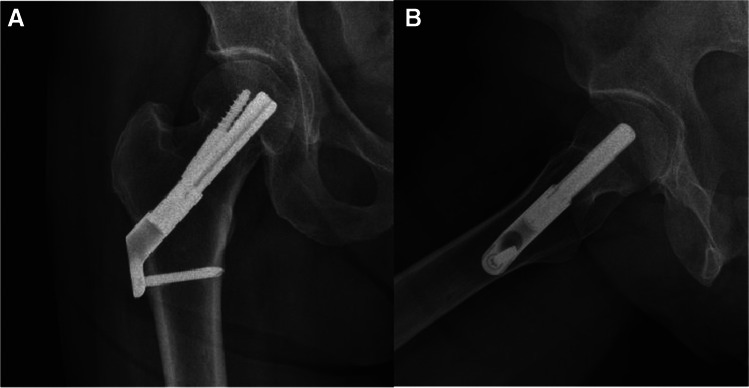

Fig. 7.

A, B AP and lateral radiographs showing right intracapsular femur fracture of a 71-year-old female. An isolated injury to the right hip after falling from own height when getting out of bed. Past medical history consists of chronic lymphocytic leukaemia, walks unaided

Fig. 8.

A, B AP and lateral radiographs postoperative day 1, demonstrating fixation of the fracture with FNS

Fig. 9.

A, B AP and lateral radiographs from last follow-up, 24 months after the surgical treatment. Walks unaided, no complaints of chronic hip pain